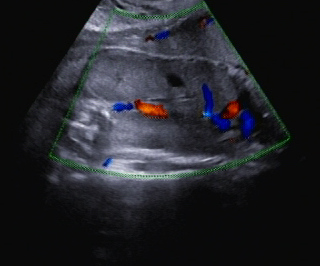

Ein zunächst durchgeführtes CTG war unauffällig. Im Rahmen der sonografischen Untersuchung zeigte sich der Fötus soweit beurteilbar zeitgerecht entwickelt. Dennoch konnte ein Anhydramnion festgestellt werden(Abb. 1, 2), weshalb auch kein fetales Gesicht darstellbar war (Abb. 3).

Im Abdomen war die Blase nicht gefüllt darstellbar (Abb. 4).

Die Nieren zeigten sich sehr stark vergrößert, beidseitig vollständig Abdomen füllend (Abb. 5, 6) und ohne Mark-Rinden-Differenzierung (Abb. 7–9). Die Lunge war hypoplastisch (Abb. 10)